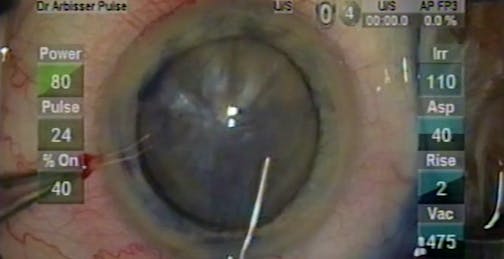

Posterior Polar Cataract My Way

Lisa Brothers Arbisser, MD